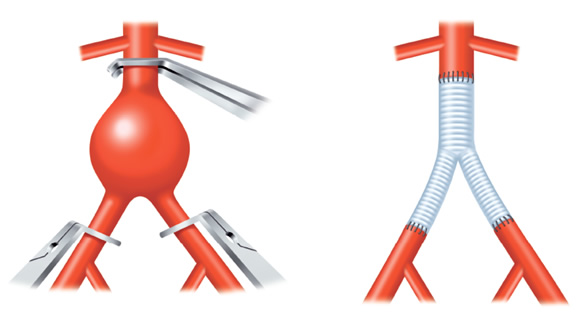

腹部大動脈瘤(AAA)からの動脈性出血では出血性ショックに至ります。鑑別を要する病気のほとんどが痛みのために血圧が上昇しますが、腹部大動脈瘤破裂は、逆に血圧が低下し、急激な貧血の進行を伴うショックバイタルになります(ここで気付けば上等)。

腹部大動脈瘤破裂が始まれば致死率は80-90%になります。

腹部大動脈瘤(AAA)があれば、周囲の動脈、特に腸骨動脈にも同じような動脈瘤が存在する可能性があります。これらはステントを留置するカテーテル手術の適応となります。